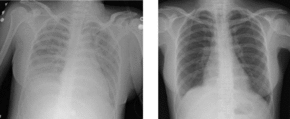

Chest x-ray of patient with ARDS | |